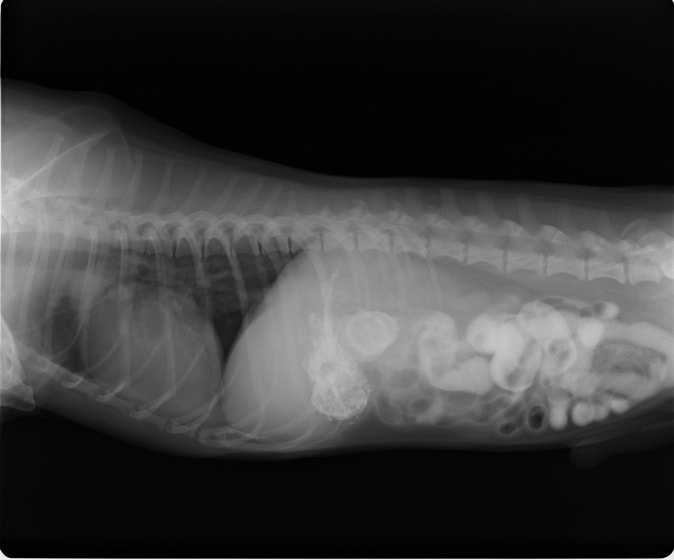

4歳 アメリカンショートヘアー

主訴:3日前から嘔吐が続き、食欲も落ちてきたのこと。

対症療法(症状に対する治療)に反応しないため、精査を実施。

一般血液検査:問題なし

単純レントゲン検査:胃内ガス陰影・腸内ガスが少量認められる。

嘔吐が改善しないため、消化管バリウム造影検査を実施。

消化管バリウム造影レントゲン

バリウム造影3時間経過するも、胃内からバリウム排泄なく同日内視鏡検査を実施。

内視鏡検査結果:内視鏡下にて、バスケット鉗子を用いて摘出。

症例は、机の上に置いていたピスタチオのお菓子を誤飲していました。その後の経過は良好です。本症例は、内視鏡下にて摘出ができましたが、球状・立体などの大きな異物は、腸の途中で詰まりやすく、内視鏡下での摘出が困難な場合もあります。その際は、開腹下にて腸内の異物を摘出しなくてはなりません。動物たちは、思わぬ物を誤飲することがあります。お留守番時・就寝時は、誤飲をしやすい時間帯ですので注意しましょう。